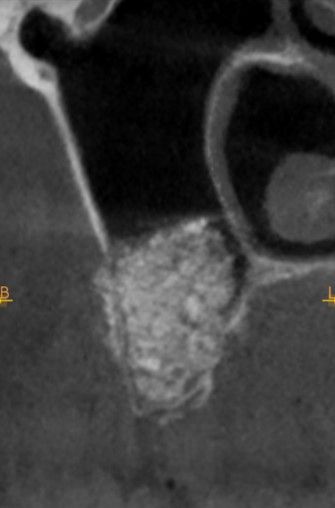

En la exploración radiográfica mediante escáner se apreció una lesión apical de pequeño tamaño en el 1.4 y una escasa disponibilidad ósea. Además, se observó imagen radioopaca cupuliforme de 3 x 2,8 cm en el seno maxilar derecho, compatible con un pseudoquiste sinusal (Figura 2). La extensión craneal alcanzaba la mitad superior del seno maxilar y el volumen de la lesión (5 cm³) era aproximadamente ⅓ del volumen sinusal (Figuras 3 y 4).